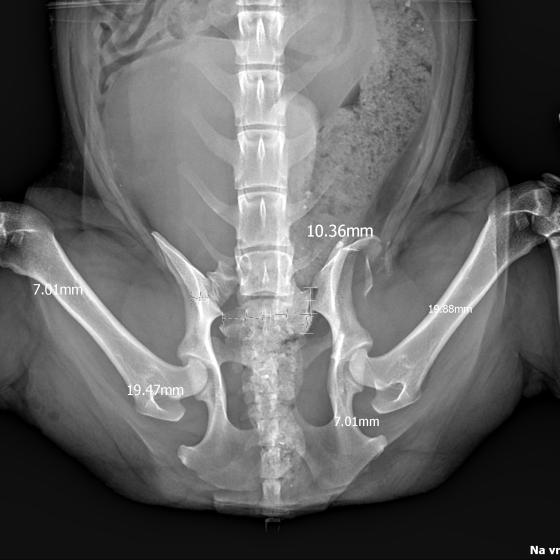

Karola nám doviezla pani, ktorá ho našla, asi jediná dobrá duša, ktorá pri ňom neprešla so zatvorenými očami. Ihneď sme s krpcom utekali na veterinu aby sa zistila závažnosť jeho zranení. Hneď pri prvých RTG snímkoch sa ukázala obojstranná fraktúra panvy, taktiež fraktúra krídla panvy a keby mu to chudákovi nestačilo, do tretice sa objavila zlomenina stavca. Karolko mal neznesiteľné bolesti, ale krásne prečkal vyšetrenie lebo vedel, že je v dobrých rukách a dostáva sa mu pomoci. Po nálezoch sme okamžite kontaktovali neurológiu a ortopédiu na veterinárnej klinike Sibra - centrum veterinárnej medicíny, kde sme dostali hneď termín na príjem.